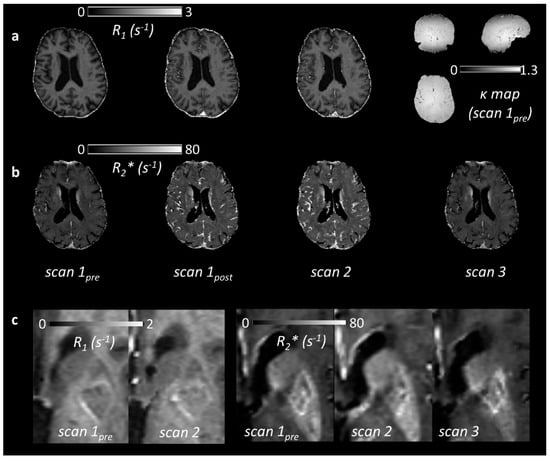

2.3. Relaxation Rate Changes Following USPIO Administration

| ROI | R1 (s−1) | R2* (s−1) | |||||

|---|---|---|---|---|---|---|---|

| Scan 1pre | Scan 1post | Scan 2 | Scan 1pre | Scan 1post | Scan 2 | Scan 3 | |

| blood | 0.526 (0.036) | 3.672 (0.629) *** | 4.665 (1.140) *** | - | - | - | - |

| WM | 1.090 (0.034) | 1.123 (0.022) ** | 1.129 (0.032) *** | 19.3 (0.7) | 22.1 (0.4) *** | 23.0 (0.8) *** | 19.3 (0.7) |

| GM | 0.825 (0.036) | 0.907 (0.022) *** | 0.908 (0.041) *** | 19.1 (1.3) | 24.9 (1.5) *** | 26.6 (2.2) *** | 19.3 (1.0) |

| WMH | 0.905 (0.075) | 0.983 (0.061) * | 0.967 (0.067) *** | 16.5 (1.1) | 19.7 (1.0) *** | 20.5 (1.6) *** | 16.6 (1.1) |

| SL | 0.926 (0.108) | 1.002 (0.116) * | 0.989 (0.102) *** | 19.0 (3.6) | 21.4 (2.5) ** | 23.9 (4.6) *** | 19.3 (3.7) |